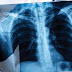

دكتور محمد مصطفى عبدالهادي التسميات : أمراض صدرية دكتور محمد مصطفى عبدالهادي تخصص أمراض صدريةاضغط هنا للاتصال